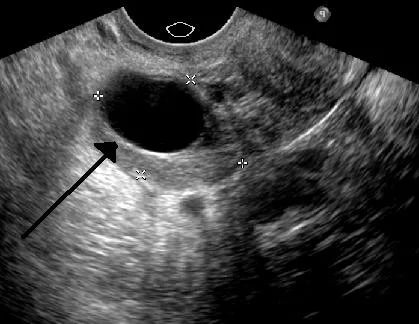

Затем обязательно назначается ультразвуковая диагностика органов малого таза. Также это исследование помогает выявить патологии внутриутробного развития плода, если женщина беременна.

На УЗИ выявляется большие затемнения, которые могут указывать на развитие тератомы